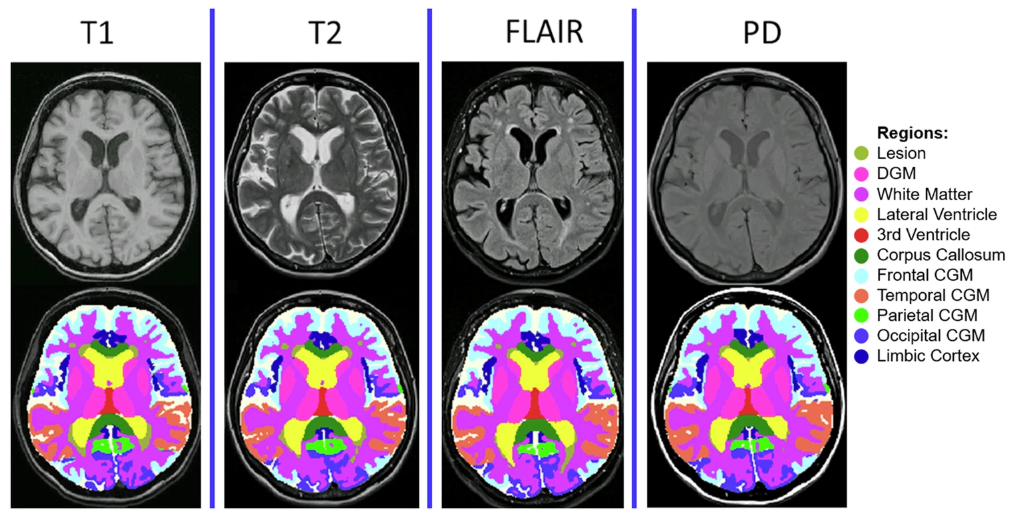

*MindGlide 通过医院档案中常用的 MRI 对比和相关组织强度(T1-weighted、TI-weighted、Proton Density (PD) 和 T2-Fluid Attenuated Inversion Recovery (FLAIR))处理 MRI,包括 2D 和 3D 扫描。

其中,PPMS 数据集包括 11,015 个 MRI 扫描(2,756 个 TI-weighted、2,754 个 T2-weighted、2,749 个 FLAIR、2,756 个 PD),所有切片厚度均为 3mm(1mm x 1mm x 3mm);SPMS 数据集包括 763 次扫描(378 次 TI-weighted、385 次 T2-weighted),具有不同的切片厚度(T1-weighted 为 1mm x 1mm x 1mm;T2-weighted 为 3mm x 1mm x 1mm);儿科 RRMS 数据集包括 1,478 次扫描(523 个 T1-weighted、475 个 T2-weighted、480 个 FLAIR),包含不同的切片厚度。